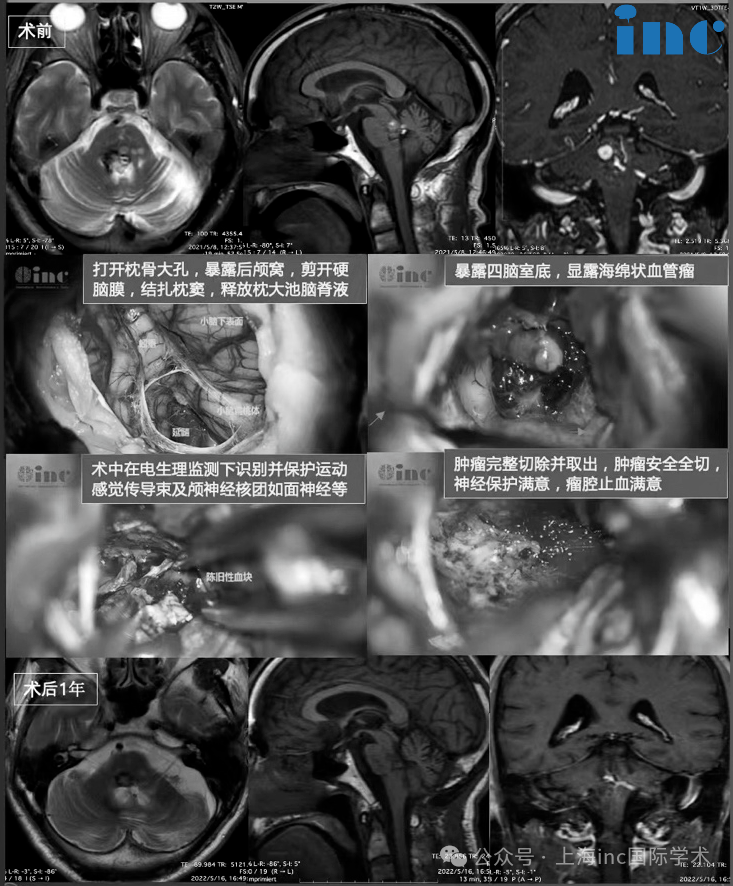

INC德国巴特朗菲教授于2021年5月来华疑难手术示范。5月21日,60岁的王先生在苏州大学附属第四医院接受了由“巴教授”亲自主刀的脑干海绵状血管瘤切除术。导致王先生反复出血的脑干海绵状血管瘤病灶得到全切,王先生术后第二天就转出了ICU,术后第三天就可下床活动,可正常进食,无新发神经功能损伤,术后两周出院。

由于反复出血是造成脑干海绵状血管瘤患者伤残和死亡的重要原因,部分切除的病例再出血可能性较大,可引起灾难性的神经功能缺失,因此,完整切除病灶进行全切手术(BSCM)是防止再出血的方法。

近年来,随着神经影像学的进步,神经导航、神经电生理监测的应用以及显微神经外科技术的进步,全切手术效果也明显提高。但医学的突破从不是坦途,需要跨越恐惧与犹疑的双重障碍,用理性构筑的决策框架,在生命的天平上及时按下正确的砝码。毕竟,生命的缰绳始终掌握在自己手中。